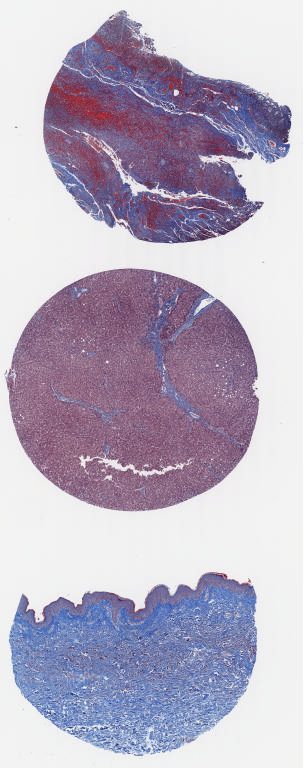

T - Trichrome.svs

16183 x 40992

@ 40X